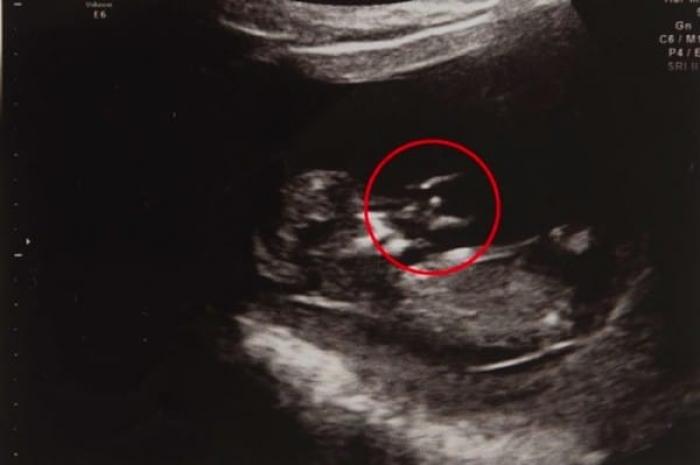

O gravidă a descoperit ceva INEDIT la ecografie! Ce se afla lângă bebelușul său este incredibil!

Jennifer este în prezent o mămică extrem de norocoasă, care se bucură de o familie minunată. Totuși, lucrurile nu au fost atât de simple pe cât par acum. Înainte de a se bucura de nașterea fiului său, femeia a trecut printr-o mulțime de situații inedite